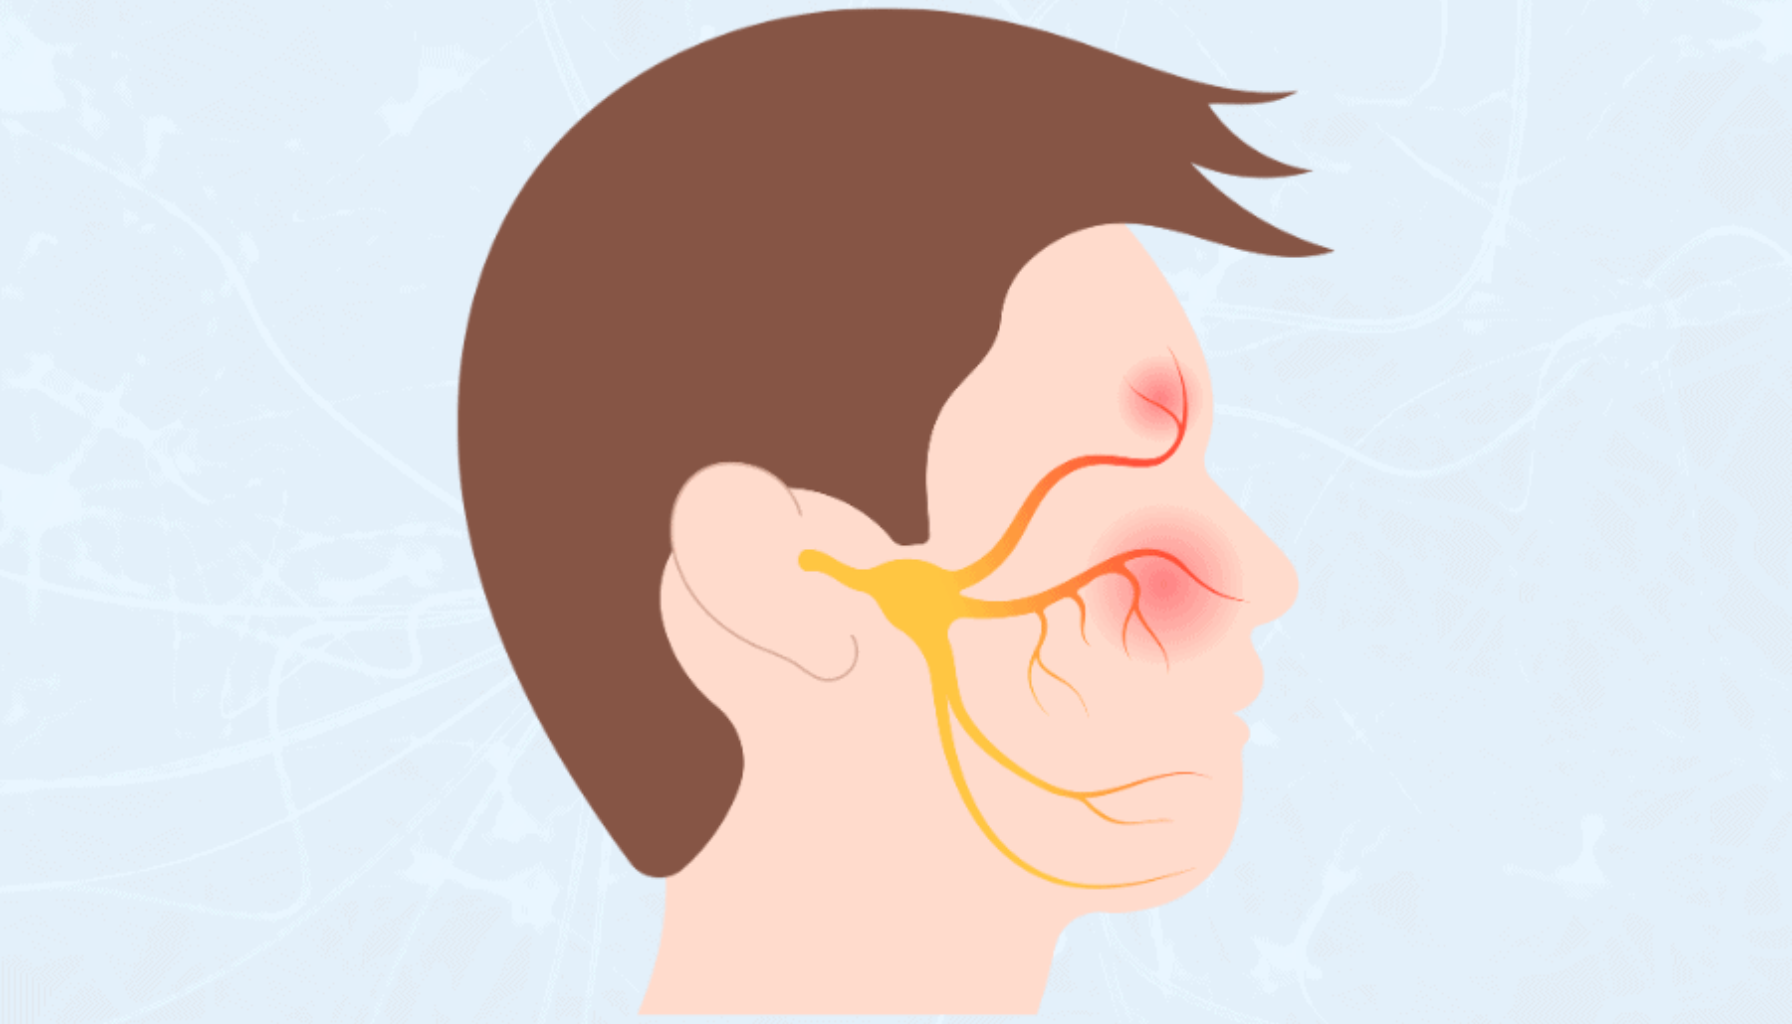

Rotfylling er nødvendig når en tann har blitt alvorlig skadet av karies, infeksjon eller traumer, noe som truer tennenes helse og funksjon. Det er spesielt viktig når infeksjonen har nådd det indre laget av tannen, kjent som tannpulpa, som inneholder nerver og blodårer. Tegn på at rotfylling kan være nødvendig inkluderer vedvarende tannverk, ubehag ved tygging eller hevelse rundt tannen. I tillegg kan misfarging eller hull i tannen indikere at det er behov for behandling.

Rotfylling er en kritisk behandling for å redde en tann som har blitt alvorlig skadet på grunn av hull, infeksjon, eller traume. Når en tann er skadet, kan den indre delen, pulpaen, bli infisert eller betent. Uten behandling kan infeksjonen spre seg, noe som kan føre til alvorlige komplikasjoner, inkludert tap av tannen, som kan ha langvarige konsekvenser for munnhygiene og generell helse.

Dersom tannen ikke rotfylles, kan infeksjonen spre seg til omkringliggende vev og føre til alvorlige tilstander som abscesser. Dette kan også resultere i betydelig smerte, hevelse, og i verste fall, tannuttrekking. I tillegg kan infeksjonen påvirke helsen til nabotennene og kjeven, og kan i verste fall føre til systemiske helseproblemer.